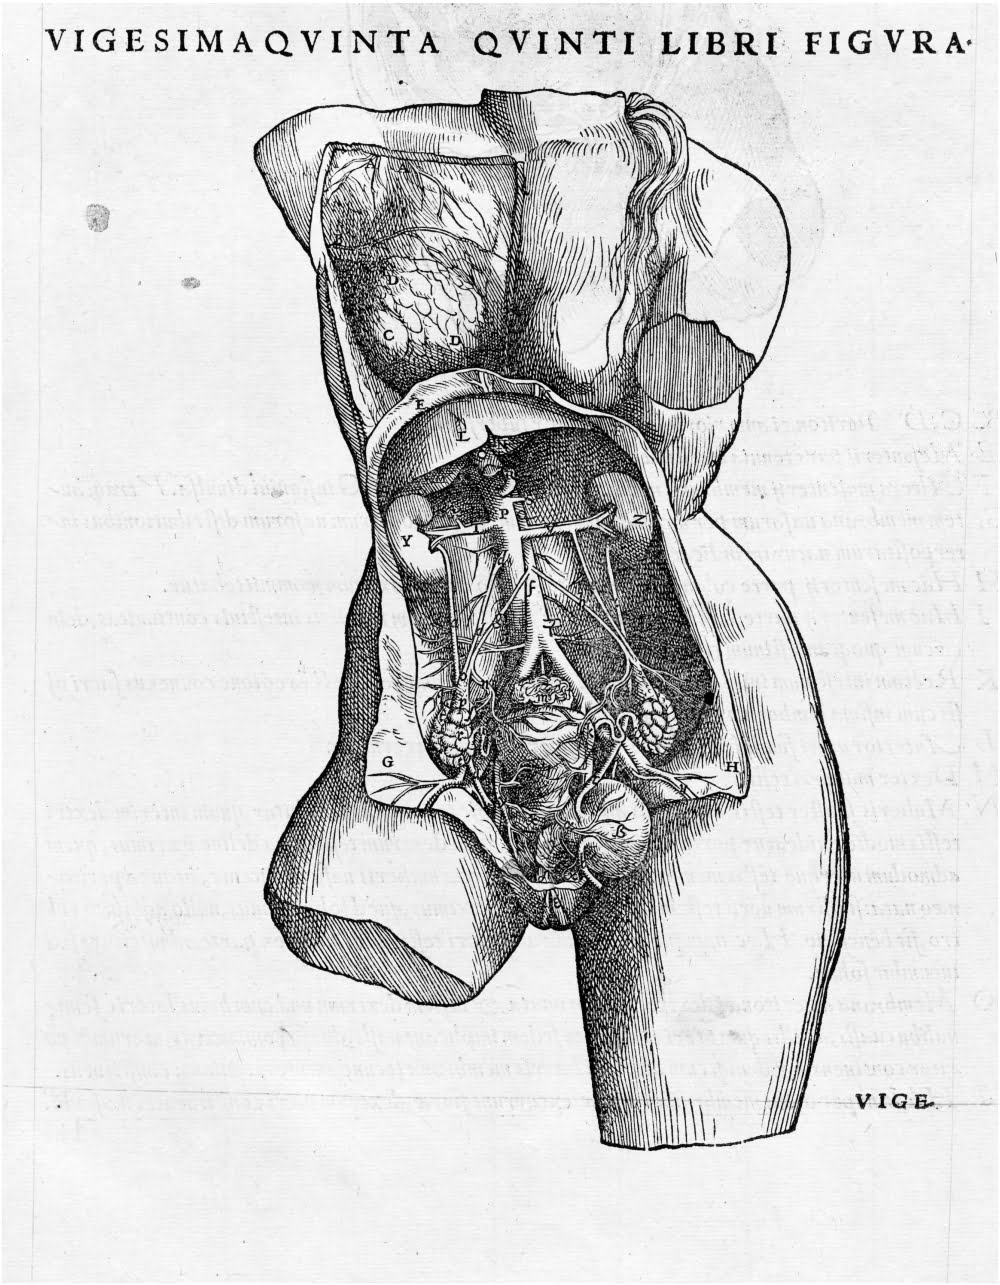

Claro que después de que se rompió con las barreras de la disección en el medioevo europeo, aparecieron publicaciones como el Isagoge breves de Berengario da Carpi (considerado por algunos como el primer anatomista) a la cual seguiría Andreas Vesalius con su De Humani Corporis Fabrica Libri Septum, el cual se convirtió en uno de los libros de mayor influencia en cuanto a anatomía humana se refiere.

De hecho, prácticamente cada fuente que se encuentre sobre dibujar Ilustración Médica hablará sobre los estudios de Vesalius y, por supuesto, de los de Leonardo Da Vinci (sobre quién contamos con una variedad de publicaciones, como la de “El dibujo a la manera de Leonardo da Vinci”).